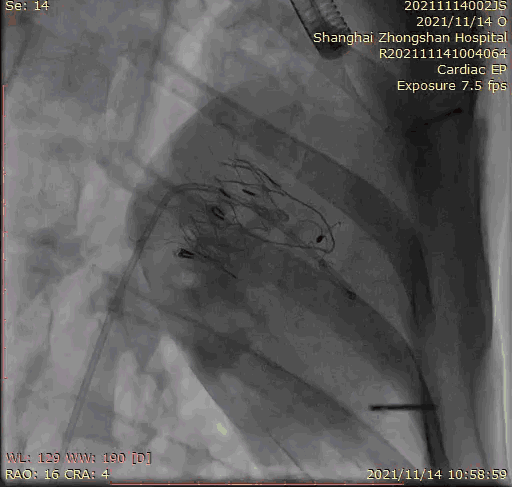

本次臨床前研究經(jīng)右側(cè)頸靜脈置入LuX-Valve Plus輸送系統(tǒng)可調(diào)彎鞘管,在DSA及超聲引導(dǎo)下將人工三尖瓣瓣膜植入到原有三尖瓣位置,利用獨特的錨定技術(shù)將人工瓣膜支架可靠固定在預(yù)定的位置。

Lux-Valve是全球第一款具有我國完全自主知識產(chǎn)權(quán)的經(jīng)導(dǎo)管介入三尖瓣置換系統(tǒng),利用前瓣夾持及室間隔錨定的復(fù)合方式進行瓣膜裝置的固定,不依賴瓣環(huán)徑向支撐力,同時采用自適應(yīng)復(fù)合裙邊材料,有效的貼合密封柔軟的三尖瓣瓣環(huán),針對于三尖瓣返流的患者有優(yōu)異的療效。Lux-Valve Plus采用全新的經(jīng)血管輸送系統(tǒng),經(jīng)頸靜脈入路創(chuàng)傷更小,可以進一步降低手術(shù)風(fēng)險。相信在后期正式臨床研究開展中,Lux-Valve Plus必定會為更多的三尖瓣反流患者帶來福音。